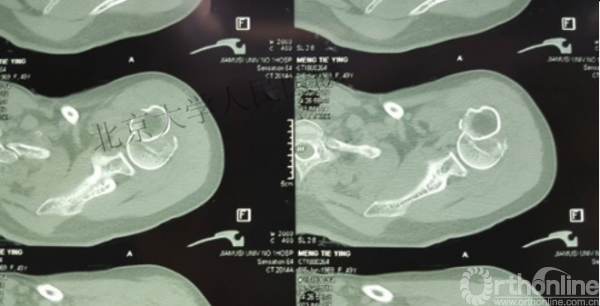

内侧皮质粉碎,低位外科颈骨折,肱骨头-干角维持困难。

术后复位丢失,肱骨头内翻畸形。

另一个留有遗憾的病例,您的选择?PHN?